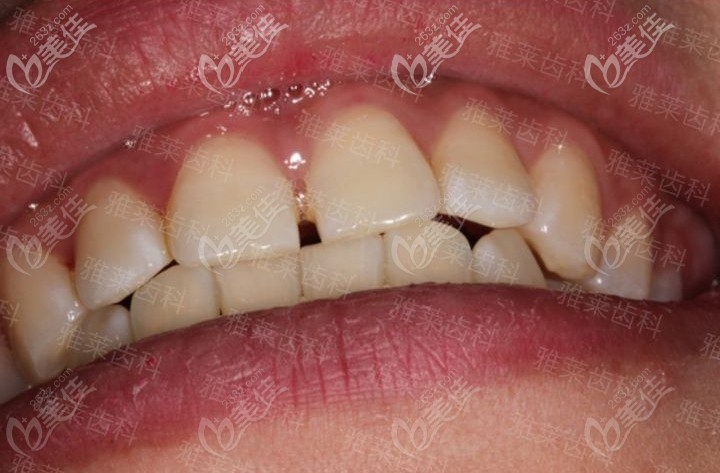

杭州雅萊齒科紀亞梅是杭州有名的牙齒矯正醫(yī)生,找她看牙靠譜嗎? b1231 G0 V0

杭州雅萊齒科紀亞梅是杭州有名的正畸醫(yī)生,很多人關(guān)注她,如果找他做隱形矯正不知道靠譜嗎?有沒有案例可參考。